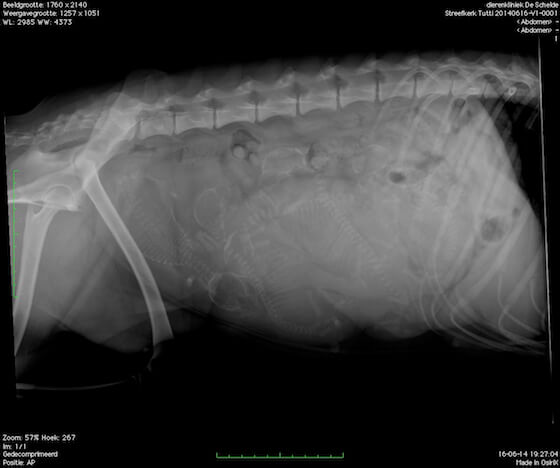

Na een röntgenfoto weten we het zeker. Tutti zal eind juni 5 puppy’s krijgen!

1, 2, 3, 4 & 5.